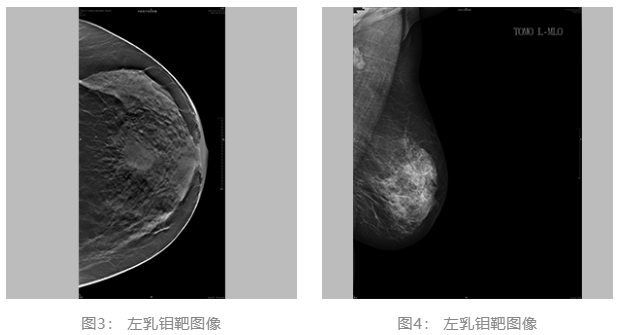

2021.06.30 乳腺彩超:左侧乳腺低回声团块,BI-RADS-US 4c类。左侧腋窝肿大淋巴结。(图1、2)

乳腺彩超: